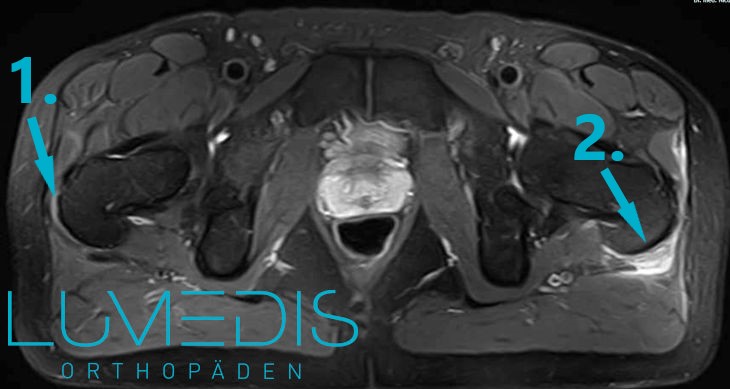

MRT (T2) beider Hüftgelenke

MRT vom Becken mit Muskelbündelriss vom M. gluteus medius / maximus links